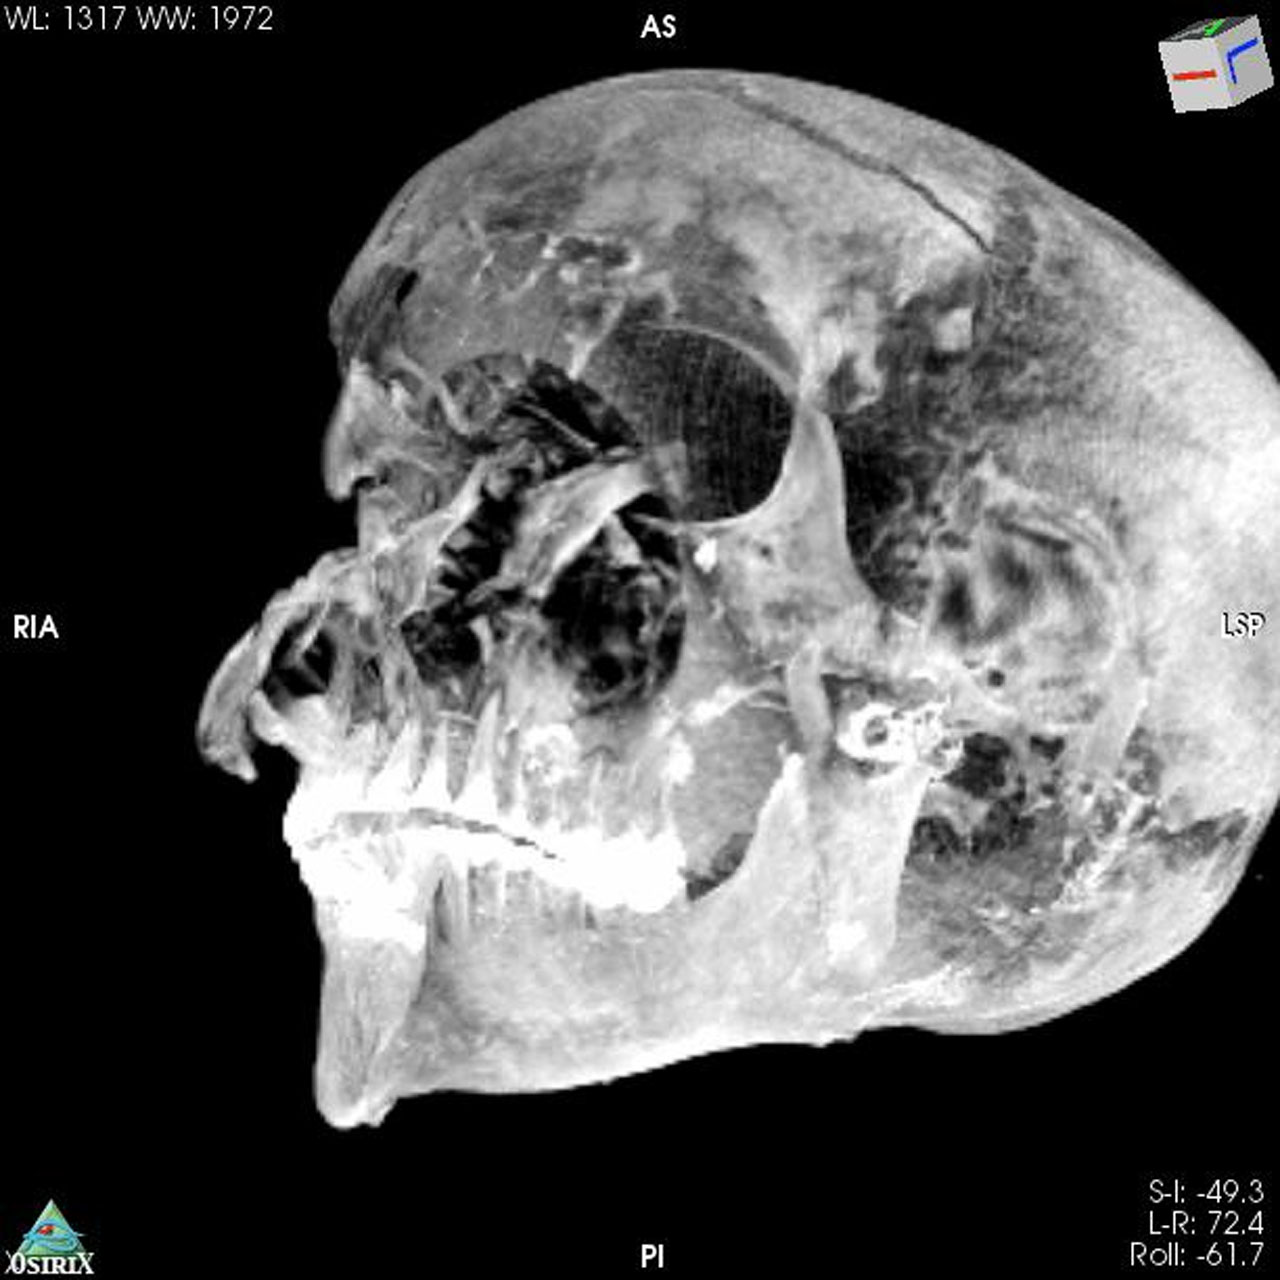

The mummified remains were first discovered and studied in the 1880s. Since the discovery of the mummy, scholars have wondered about the exact nature of Seqenenre-Taa-II's death. In the 1960s, the mummy was examined using x-rays that found severe head injuries and no other wounds to the body.

The CT scans discovered something interesting in the form of previously undetected lesions that embalmers concealed. The new paper has found that the pharaoh was likely captured on the battlefield, and his hands were tied behind his back to prevent him from defending against the attack. The team believes that the death of Seqenenre-Taa-II was a ceremonial execution.

The ancient pharaoh was about 40 years old when he died, based on morphology revealed in the new CT images. CT images also revealed that the embalmers used a sophisticated method to hide the head wounds under layers of embalming material that functioned like fillers used in plastic surgery. The researchers believe the mummification took place in a real mummification laboratory rather than being performed hastily as previous studies suggested.